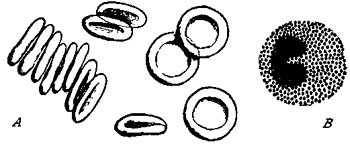

109 Blood Corpuscles

112 Surface Veins and Deep-Lying Arteries of Inner Side of Right Arm and Hand

114 Diagram of Artery, Capillaries, and Vein